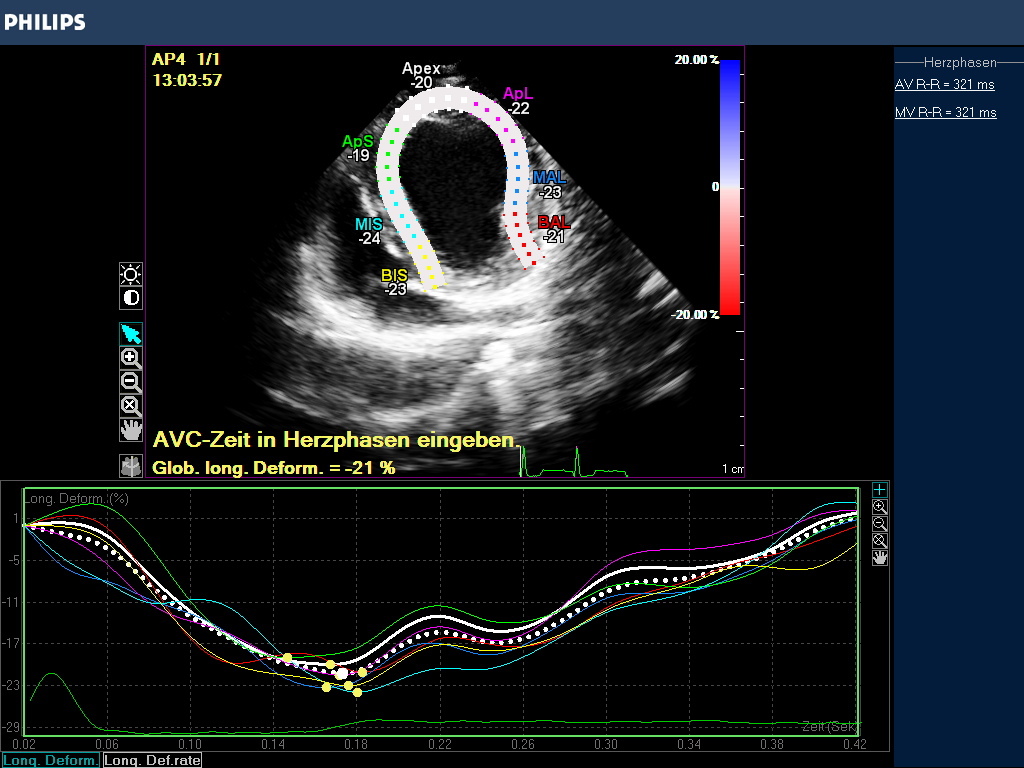

In praxi wird das Myokardium (LV/RV oder Atrien) in 7 Segmente unterteilt, die z.B. für den linken Ventrikel eine Hufeisenform annehmen, die Grenzen dieser enddiastolischen Region Of Interest (ROI) können manuell korrigiert werden über die Software des Geräts. Erfasst wird die endokardiale -, epikardiale Grenze und die myokardiale Mittellinie. Die Akquise der Werte erfolgt automatisch, semiautomatisch oder manuell. Die Einbeziehung des Perikardiums kann zu einer Reduzierung der Strainwerte führen! Die ROI Segmente bekommen Farben und Kürzel zugeordnet (Tabelle 1, Abb.2), die für Myokardsegmente stehen und so können nicht nur globale sondern auch regionale Dysfunktionen erkannt werden.

Der Gerätemonitor gibt die Strainmessergebnis in Form einer Kurve an , deren wellenförmige Line den Farbsegmenten entspricht und die zeitliche Veränderung der Strain beurteilbar macht. Jede ROI hat auch hier ihre definierte Farbe und der Durchschnittswert wird in einer globalen Strain Kurve als weiße Punktlinie angezeigt. Der Anteil der einzelnen Segmente an der GS ist abhängig von ihrer Größe. Das Maximum der globalen Strain GS wird als globale longitudinale Strain definiert (GLS).

Das Ergebnis der GLS wird in negativ -%- Zahlen angegeben. In besonders schwer erkrankten Fällen kann die Zahl positiv werden! Je höher die negative Zahl angegeben wird desto stärker ist die Verformung bzw. Kinesie des Muskels. Darüber hinaus wird nach der Simpson Methode eine Ejektionsfraktion ermittelt , die in EF % angegeben wird (Abb. 3).

Der Kardiologe erhält demnach Aussagen über die regionale Verformungsleistung des Myokards und seine Auswurfleistung. Damit liegen wichtige Werte zur Beurteilung der Inotropie des Herzmuskels vor, die für Diagnostik und Therapie wesentlich sind. In einer praxisinternen Auswertung von 40 asymptomatischen und befundfreien Patienten lag die GLS, ermittelt mit aCMQ Software, zwischen -15 und -25%. Ejektionsfraktionen nach Simpson zwischen 40 und 55%.